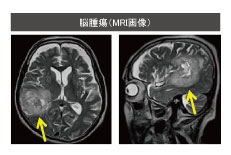

脳ドックで脳腫瘍・脳梗塞・脳動脈瘤の早期発見をしましょう。

脳神経疾患(脳腫瘍・脳梗塞・脳動脈瘤)の早期発見に脳ドックをお勧めします。

- 脳腫瘍・脳梗塞・脳動脈瘤などが発見されます。